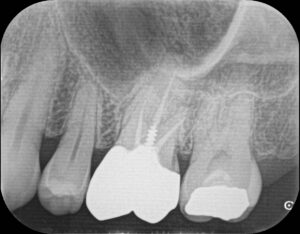

「感染根管治療」は“Retreatment”と言われ、過去に神経の治療がされている歯の治療↓になります。

→

過去に治療をされている歯は削られている範囲が大きかったり被せ物の隙間からむし歯になっていることが多いため、感染根管治療の方が抜髄に比べると治療の難易度があがり、成功率は低くなります。